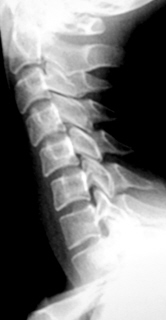

Иллюстрации 1, 2, 3. Определяется «выпрямленность» шейного лордоза, неравномерное сужение межпозвонковых щелей в сегментах С2-С3, С3-С4. Резкое сужение межпозвонковых щелей в сегментах С4-С5, С5-С6, С6-С7, с выраженным субхондральным склерозом тел позвонков, неровностью замыкательных пластинок, образованием остроконечных остеофитов по передней поверхности тел позвонков. В дугоотросчатых суставах определяется сужение суставных щелей с выраженным субхондральным склерозом. На иллюстрации 2 хорошо дифференцируется остеосклеротическая перестройка тел С4, С5, С6, С7, как компенсаторная приспособительная реакция, в результате анатомической и функциональной несостоятельности межпозвонковых дисков.